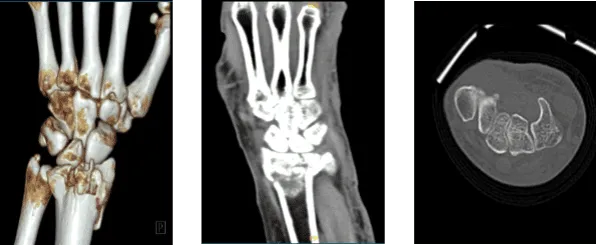

The patient presented today is 68-year-old, female and having a complaint of her left hand and wrist after getting injured because of a fall. Her Xray result showed a fracture but we wanted to make sure of the diagnosis. We agreed to take CT-Scan.